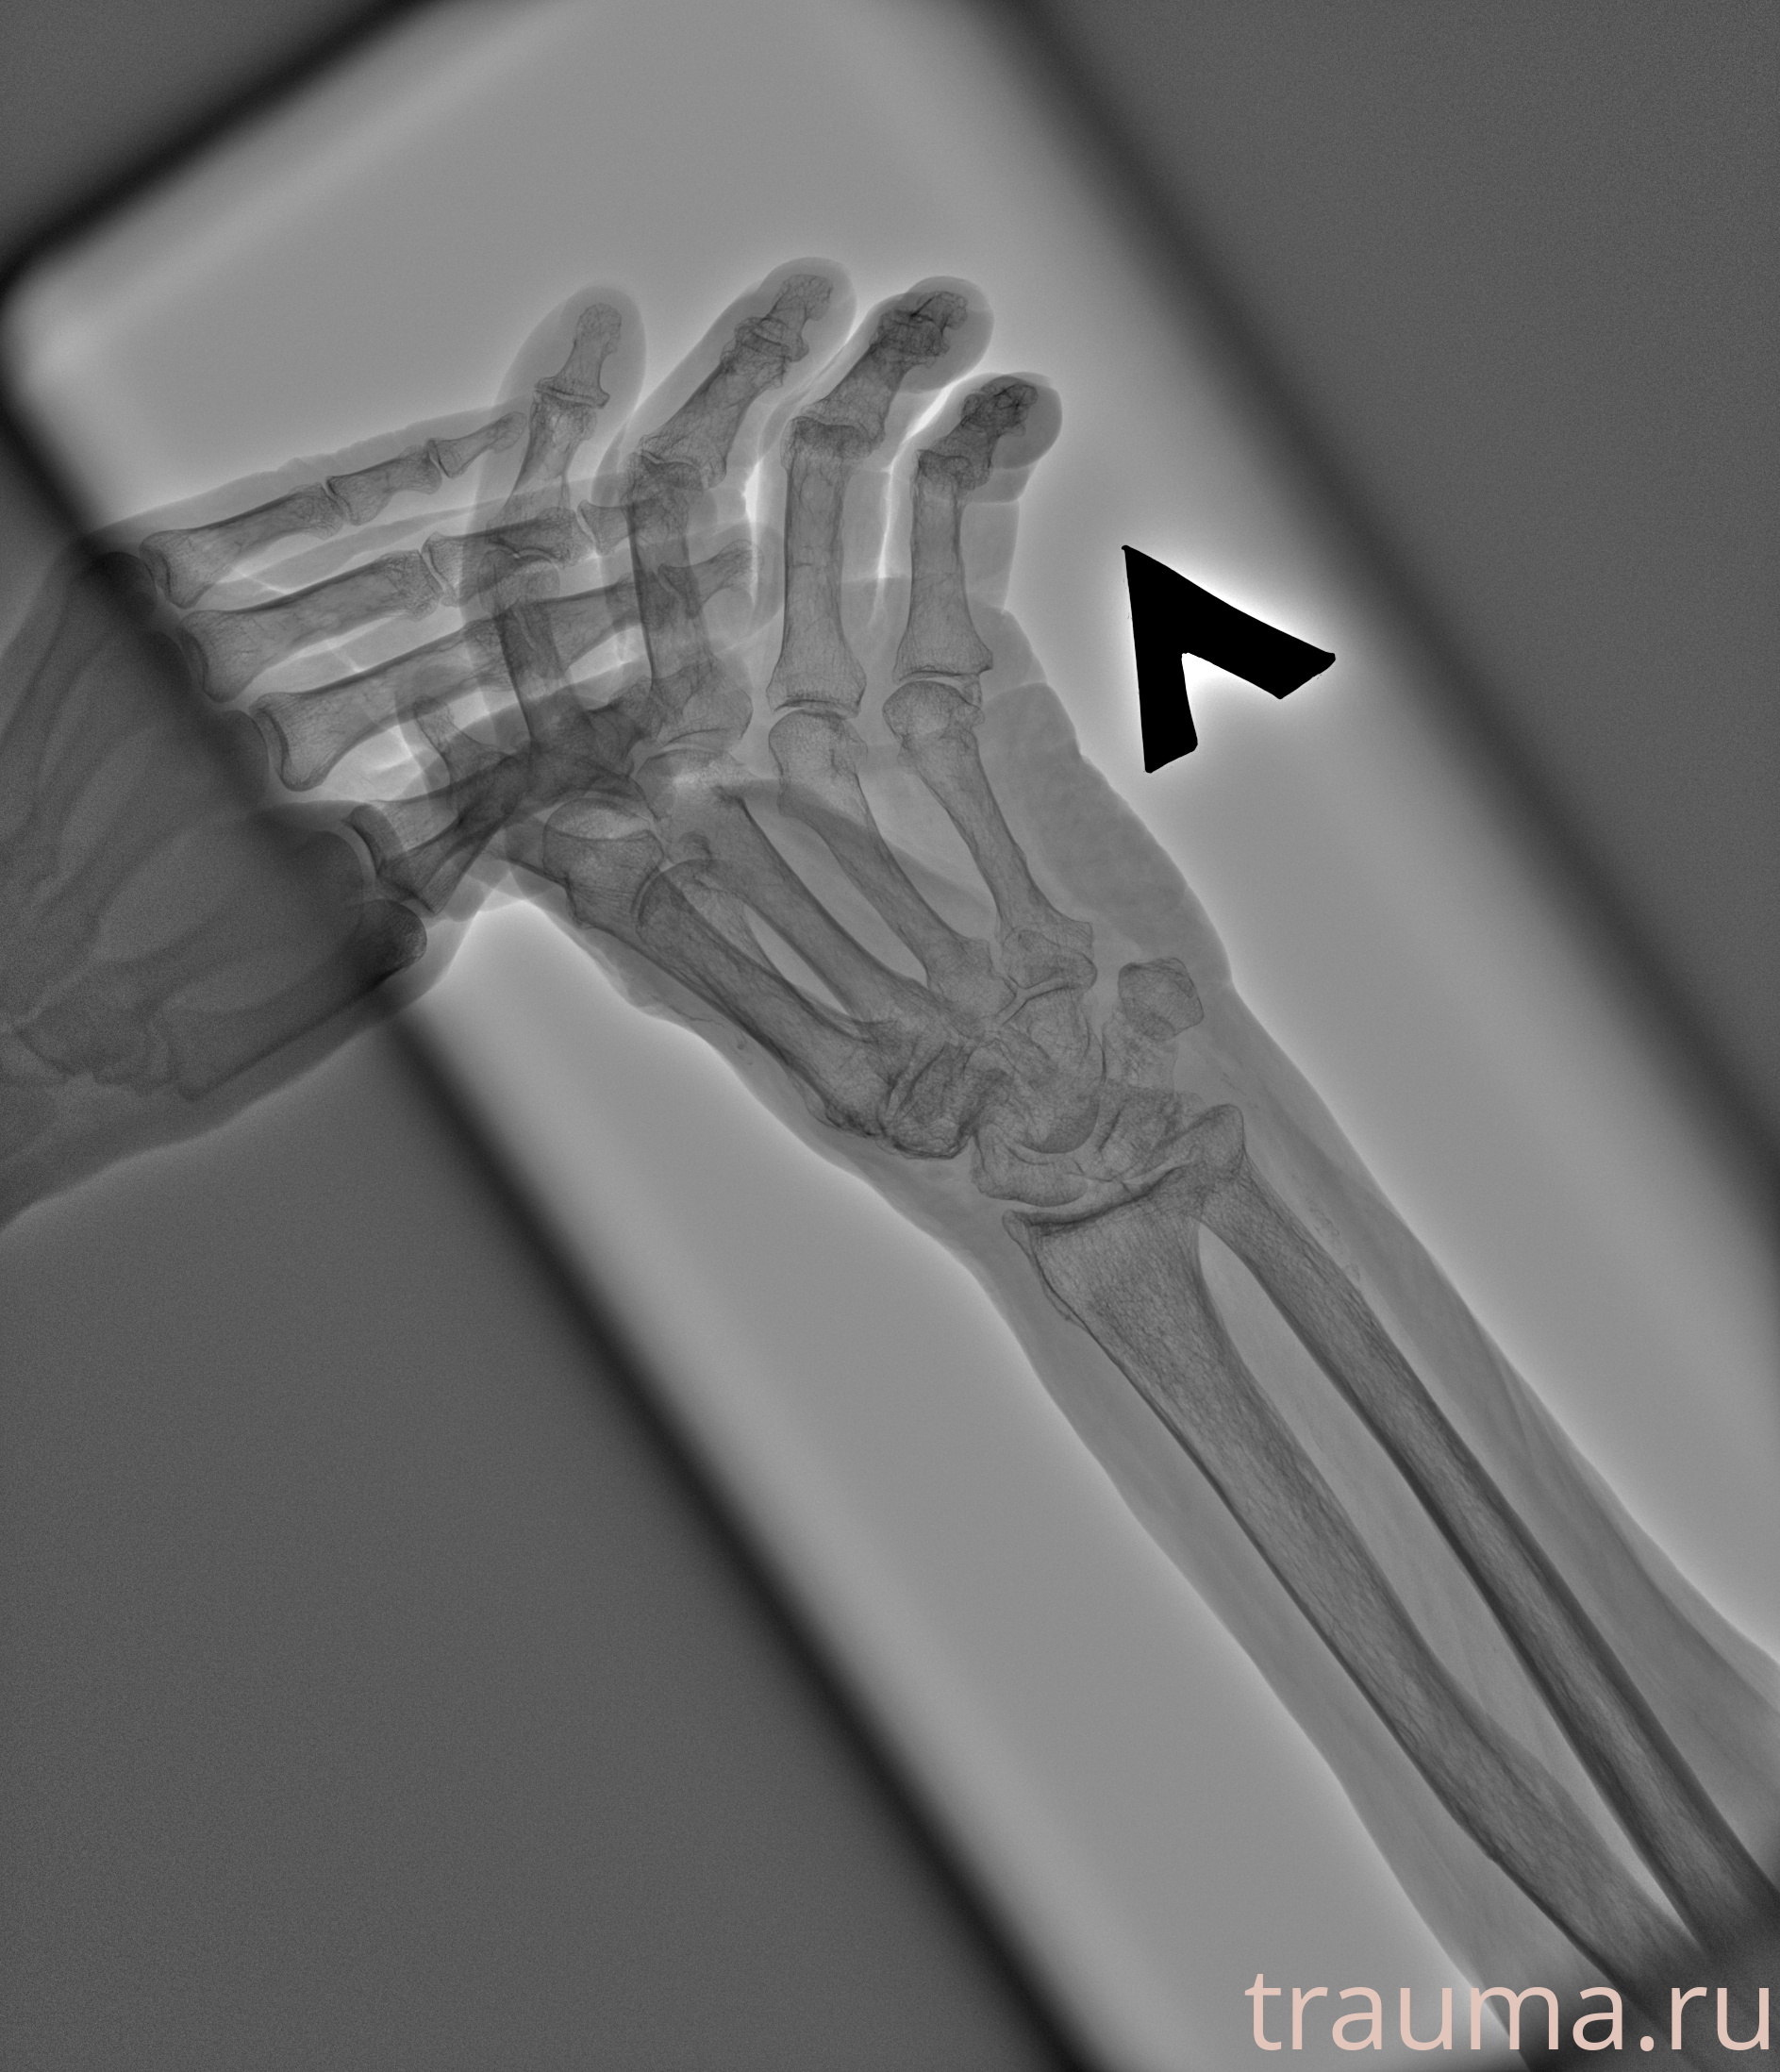

Рентген на дому: по вашему адресу приезжает врач-рентгенолог, травматолог-ортопед с мобильным рентгеновским аппаратом, проводит диагностику травмы или заболевания, делает необходимые рентгенограммы, дает рекомендации по дальнейшему лечению. Получить качественные снимки в домашних условиях возможно благодаря уникальной методике, разработанной МосРентген Центром для института  Склифосовского